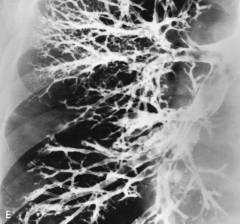

По сравнению с левым правый главный бронх короче, шире и расположен более вертикально. По мере увеличения порядка бронхов они уменьшаются в диаметре; обструкция и патологические изменения отсутствуют.

Что видно в норме?

- бронхиальное дерево имеет правильную конфигурацию;

- правый главный бронх короче, шире и имеет вертикальный ход, а левый - длиннее, уже и проходит более горизонтально;

- все бронхи имеют нормальную ширину;

- ширина бронхов постепенно сужается по мере ветвления;

- не обнаруживается никаких теней или полостей, заполненных контрастом;

- не обнаруживается сужений бронхов.

Нормальное состояние бронхов означает, что на снимке бронхографии бронхиальное дерево сохраняет правильную форму и текстуру, главные бронхи имеют обычную для них форму, толщину и положение, по мере ветвления толщина всех бронхов постепенно уменьшается, на снимке отсутствуют тени или полости, заполненные контрастом, или нетипичные сужения бронхов.